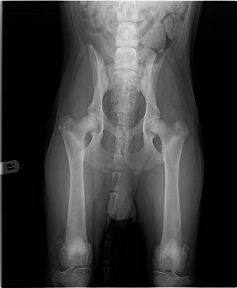

Zijn heupen bleken keurig in orde. (foto rechts) Zijn ellebogen waren ook in orde maar er was duidelijk sprake van groeipijn. Dit is zichtbaar bij de rode pijlen als een "wolking" in het

bot.